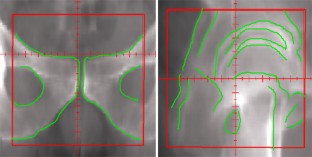

Abb. 1